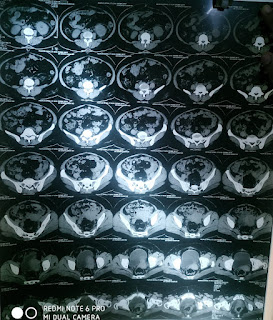

Acute lt pyelonephritis - emphysematous

A: ACUTE PYELONEPHRITIS - EMPHYSEMATOUS WITH DIABETES MELLITUS